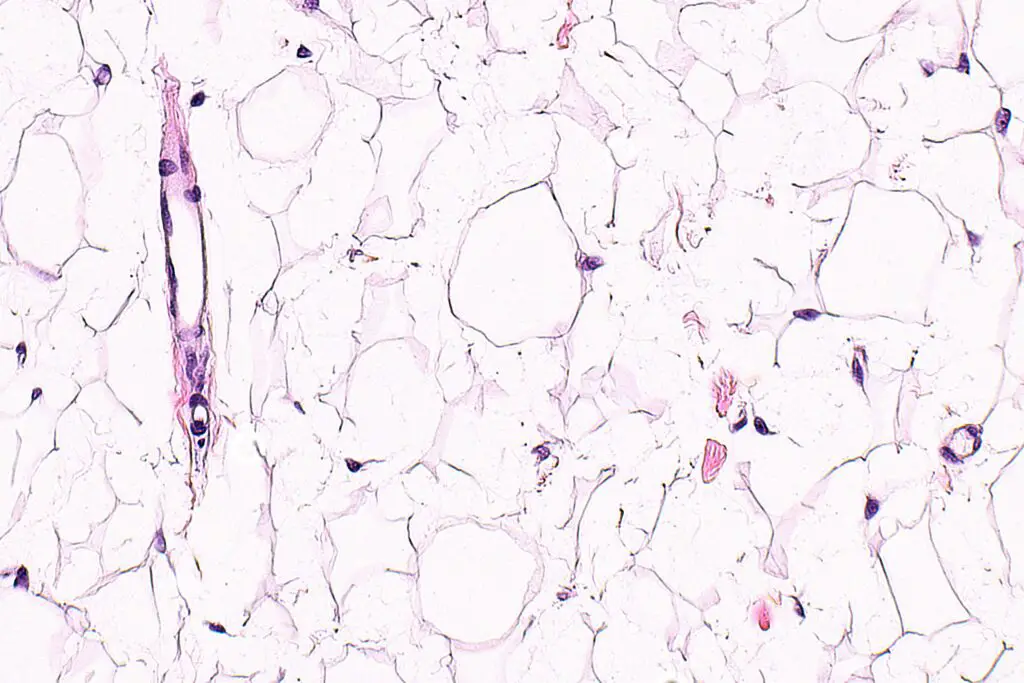

Definitive diagnosis of lipoma is made by pathology showing a well circumscribed mass composed of benign adipocytes.

Definitive diagnosis of liposarcoma is made by pathology showing malignant proliferation of adipose tissue.